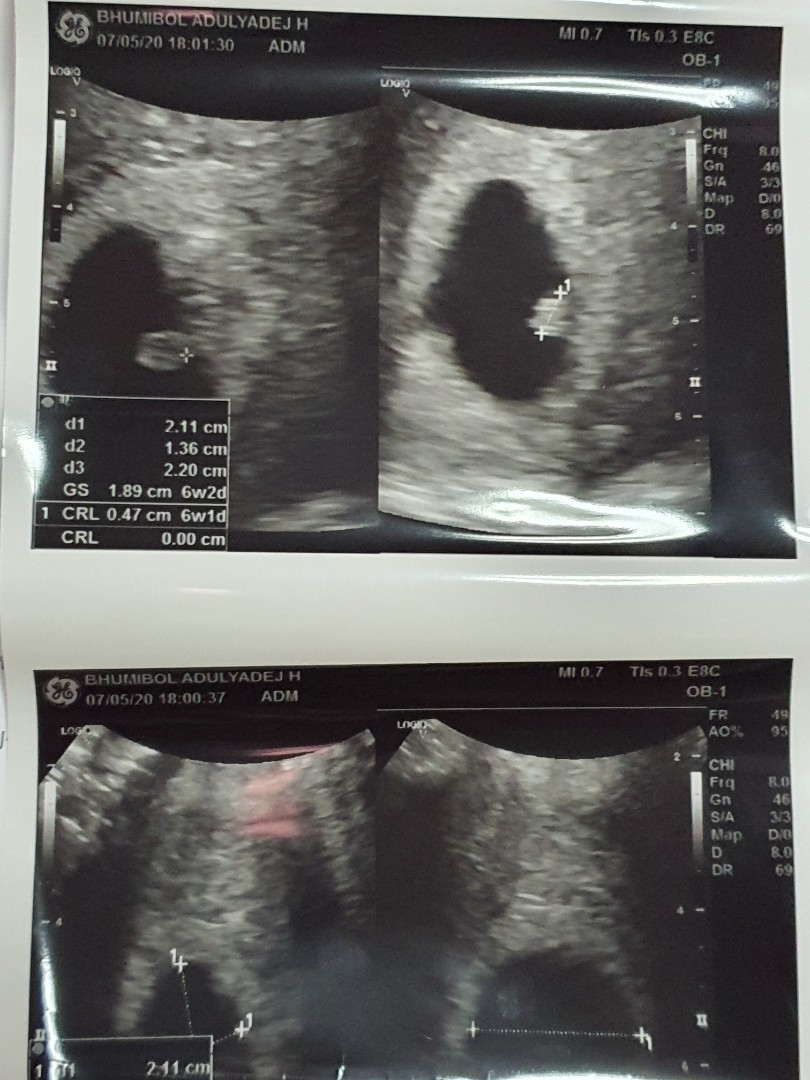

ขอดูใบซาวหน่อยจ้า เเล้วกำหนดคลอดวันที่เท่าไรกันค่ะ

20ธันวาค่ะ

20ธันวาจ้า